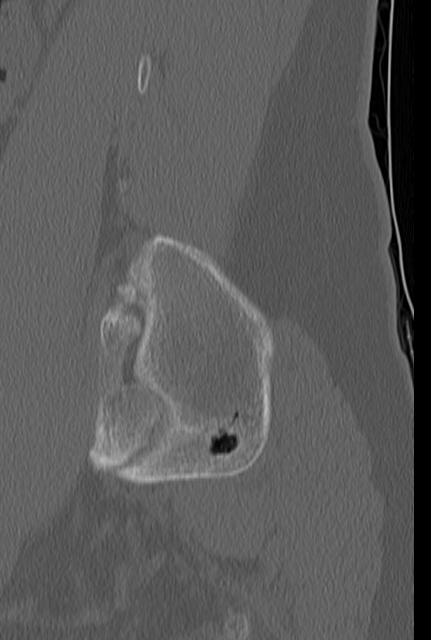

ct상 뼈에 구멍이 나보이는데 뭘까요?

현재 2달 조금 넘게 허리통증으로 외래진료 받는중인데 차도가 없어 ct를 촬영했는데 우연하게

골반뼈에 구멍 같은걸 발견했어요. 심각한 문제일까요?

선천적 이상일수도 있지만 이전 염증 및 감염 등의 흔적일 수도 있겠습니다.

뼈 안에도 물혹(낭종)이 생길 수가 있습니다. 허리 통증과는 큰 관련이 없을 수 있습니다. 치료도 대부분은 필요하지 않구요.

• CT 소견만 놓고 정확한 상태를 알기는 어렵지만 골반 뼈 부위에 비어있는 구멍이 있는 것으로 보이며 이외에 특이 소견은 보이지 않습니다. 허리 통증과 무관해 보이며 당장 큰 문제가 있다고 보기에는 애매합니다.